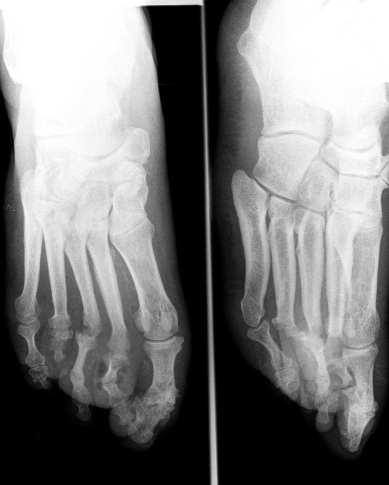

cosa sono le articolazione

1) calcificazioni lineari o a piccoli segmenti o puntiformi (dipende dalla proiezione) provengono da depositi di calcio all'interno dei tubi galattofori. La calcificazione un accumulo graduale di calcio in una zona del tessuto corporeo.